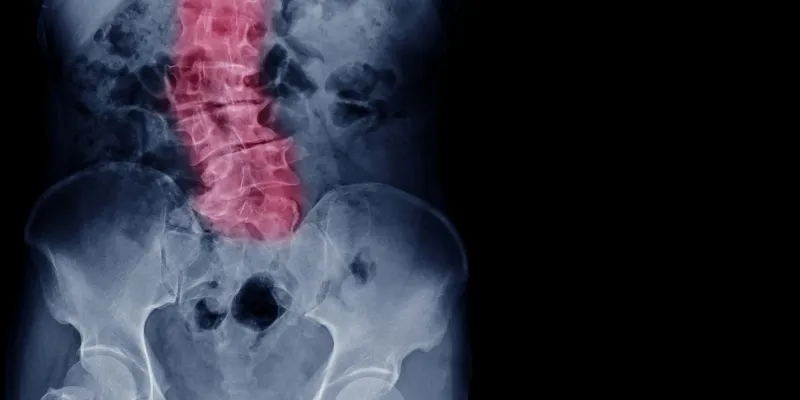

Skoliose betyder en rygradskrumning med sidebøjning af rygraden, som gør at brystkassen taber sin symmetri. Undertiden er rygradskrumningen medfødt, og ind imellem skyldes den hindringer i normal udvikling som f.eks. lammelser eller svagheder i støttemuskulaturen.

Netop i puberteten kan ryggen uden nogen kendt årsag blive skæv hos en tidligere helt rask person. Skoliose er ti gange mere almindelig blandt piger end blandt drenge.

Selv om rygradskrumningen er ubetydelig, bør man konsultere en læge. Det er vigtigt, efter som krumningen hurtigt kan forværres. Rygradskrumningen kan i ekstreme tilfælde blive så udtalt, at pladsen til lungerne påvirkes. Langt inden dette stadium nås, kan udviklingen dog rettes op med behandling. Skoliose ses tydeligt, hvis ryggen betragtes bagfra, mens barnet bøjer sig fremad og derefter retter sig op. Skoliose opdages som regel ved helbredskontrol hos skolelægen, og man kan da i tide henvise barnet til specialistbehandling.